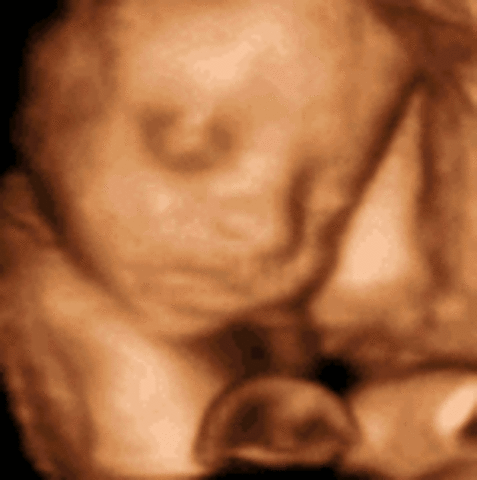

• Week 16: Facial Expressions are Possible

Week 16: Facial Expressions are Possible

Fetus measures nearly 5 inches, fetus weighs 3.5 ounces, fetus is covered with a protective soft down to regulate its temperature, fat begins to form underneath skin, baby hears external voices, sleeps and dreams